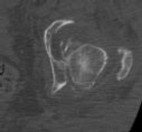

A 13-year-old obese boy presents with non-traumatic knee pain and is noted to have an obligate external rotation of his hip when it is passively flexed. Radiographs confirm the diagnosis. He is unable to bear weight on the affected extremity. What is the primary complication associated with this presentation compared to a patient who is able to bear weight?

Options:

- Chondrolysis

- Avascular necrosis (AVN) of the femoral head

- Femoroacetabular impingement (FAI)

- Slipped capital femoral epiphysis on the contralateral side

- Leg length discrepancy

Correct Answer: Avascular necrosis (AVN) of the femoral head

Explanation:

The patient has an unstable slipped capital femoral epiphysis (SCFE), defined by Loder criteria as the inability to bear weight even with crutches. Unstable SCFE has a significantly higher rate of avascular necrosis (up to nearly 50% in some series) compared to stable SCFE (which has an AVN rate near 0%). Both stable and unstable SCFEs can lead to impingement or contralateral slips, but AVN is the critical distinguishing risk factor of an unstable slip.